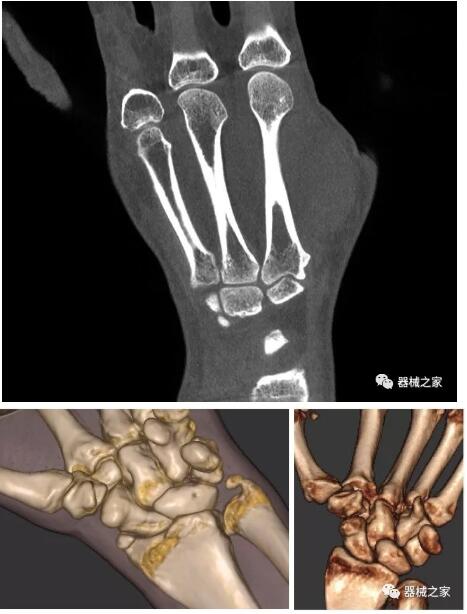

另外一款被稱為世界上最小的CT,它的重量?jī)H300磅,不僅能夠掃查足部,還可以檢查膝蓋和上肢等。

與上面介紹的CT一樣,它同樣具有輻射低、占地空間小(23*36)的特點(diǎn),隨開(kāi)隨用(支持直接接入墻上的插座)。

這款CT使用非常方便,通過(guò)上下移動(dòng)保持與患者的手臂或者雙腿齊平,掃描快速,僅需要30秒左右就可以完成掃查。

以上介紹的CT均來(lái)自國(guó)外同一家公司,這些CT均配置了可視化軟件,可以進(jìn)行切片、3D重建以及大型CT附帶的所有典型的操作功能。

以下是這些“特立獨(dú)行”的CT所拍出來(lái)的圖像: